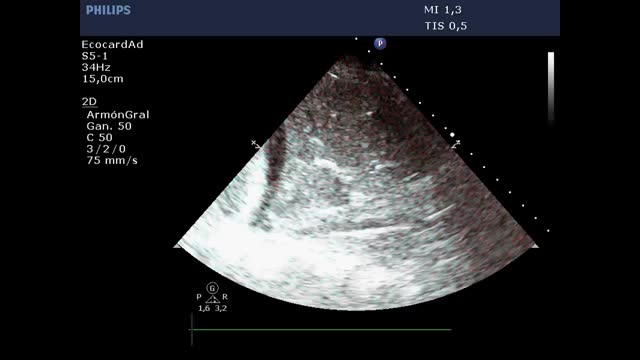

Quantification of lung aerationThe different ultrasound patterns reflect different grades of aeration (Fig. 5). In this regard, the A pattern corresponds to a normally aerated lung parenchyma. The presence of three or more B lines in an intercostal space and separated (B1) indicates moderate loss of aeration, secondary to interstitial involvement. Coalescent B lines (B2) in turn appear in cases of severe loss of aeration, secondary to alveolar involvement. When the loss of aeration is complete, we observe a consolidation pattern (C).19

Ultrasound patterns of lung aeration.

A: A lines pattern, normal aeration; B: B ≥ 3, separated B lines indicating moderate loss of aeration; C: coalescent B lines indicating severe loss of aeration; D: tissue or consolidation pattern, indicating a complete loss of aeration. Each pattern produces a score for generating the lung ultrasound score (LUS).

By dividing each hemithorax into regions and assigning a numerical value to each pattern, we can obtain a global score. The most widely used classification analyzes 12 thoracic regions (6 per hemithorax: upper and lower in the anterior, lateral and posterior quadrants).19 Each region is scored from 0 to 3 points according to the ultrasound pattern. Based on this classification, the Global Score or the Lung Ultrasound Score (LUS) ranges from 0 (aerated lungs) to 36 (lungs with total loss of aeration). In this way, variations in this score can be used to express both loss of aeration and re-aeration in different clinical situations.19,20